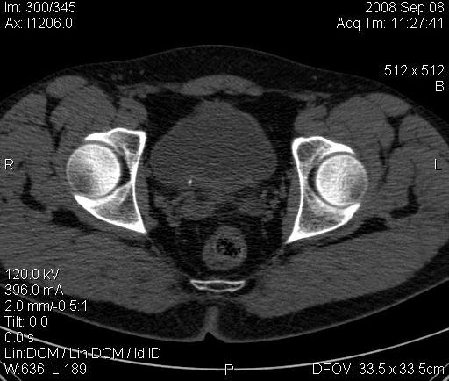

Почечная колика; на последнем аксиальном скане чётко виден мелкий (2 мм) камень в устье правого мочеточника.

Dr.Mario писал(а):Почечная колика; на последнем аксиальном скане чётко виден мелкий (2 мм) камень в устье правого мочеточника.

Да, поучительно.

Нужно смотреть все сканы. :oops: